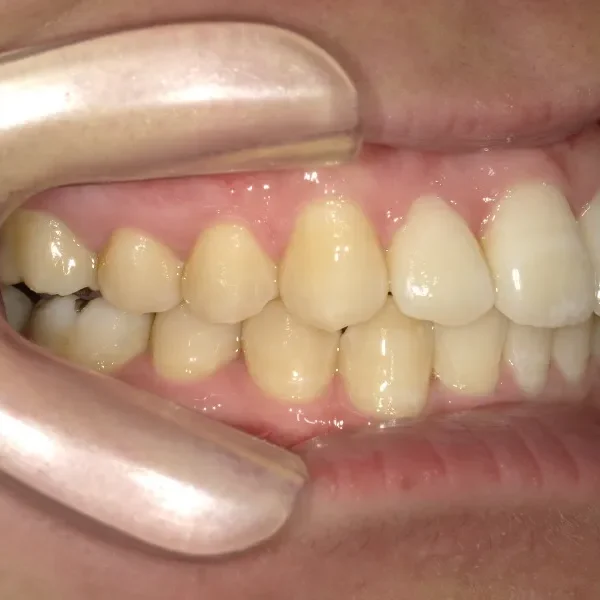

初診時年齢 19~29歳 (女性) 主訴 ガタガタ・90度ねじれている

診断名 叢生・上顎前突 装置名

奥歯が内側と前方にかたむき上下の歯がガタガタに生えています。

90度ねじれた歯もあります。前歯も出っ歯になっています。

歯は抜かず、歯科矯正用アンカースクリューを用いて治療しました。